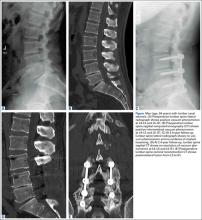

Evidence of spinal fusion was identified on follow-up CT in 32 (88.9%) of the 36 cases. In 3 of the 18 patients, nonunion was diagnosed. Of the 15 intervertebral cases in which the VP persisted, 13 (86.7%) showed evidence of fusion on CT, and 2 (13.3%) showed evidence of pseudarthrosis. Of the 21 intervertebral cases in which the VP disappeared, 19 (90.5%) showed evidence of fusion on CT, and 2 (9.5%) showed evidence of pseudarthrosis (Table 2). There was no significant difference in fusion rate or pseudarthrosis rate in the groups in which the VP persisted or disappeared (Fischer exact test, P = .99). There was no significant association between VP persistence or disappearance and sex, primary or revision surgery, or intervertebral level (Fischer exact test, P > .05). A case example is shown in the Figure.

On preoperative CT, positive VP was diagnosed in the 36 cases as follows: L5–S1 (11 cases), L4–L5 (9 cases), L3–L4 (4 cases), L2–L3 (6 cases), L1–L2 (4 cases), and T12–L1 (2 cases). On follow-up CT, 15 cases showed persistence of the VP, and 21 cases showed disappearance of the VP (Table 1).